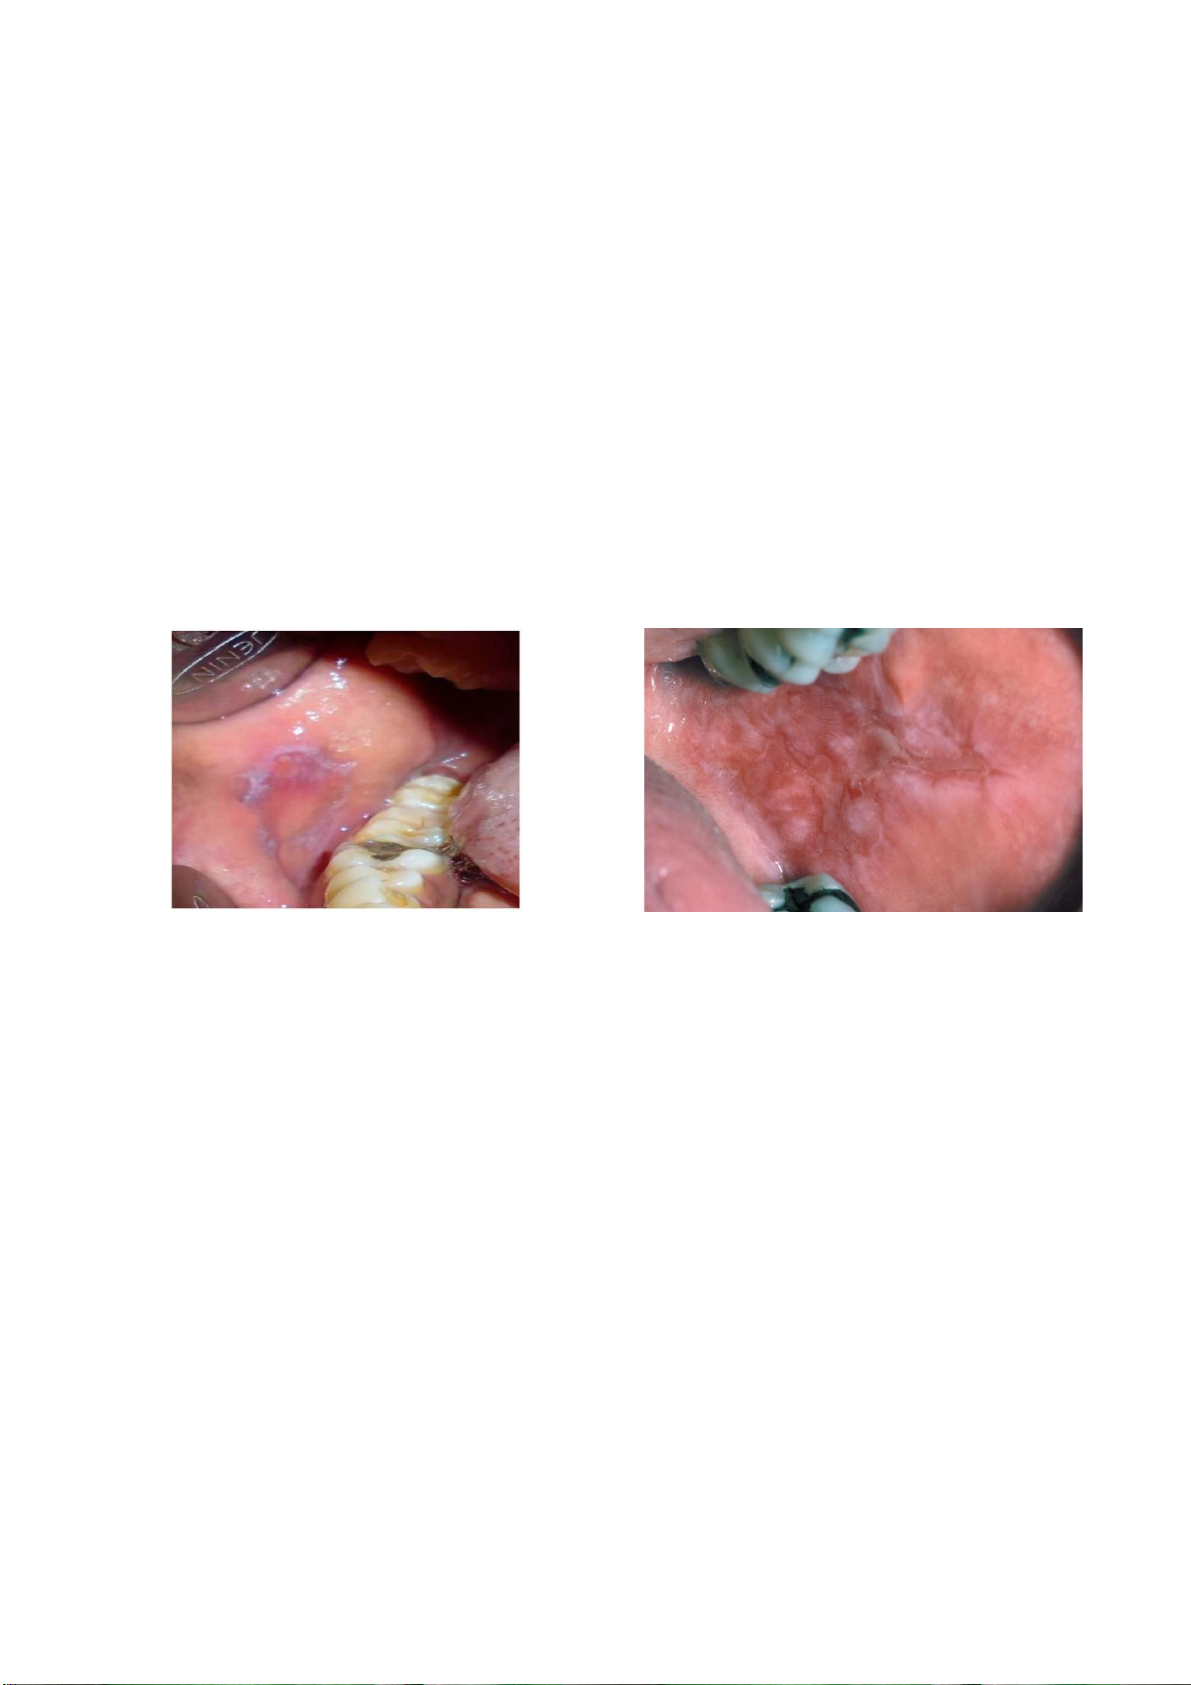

Hình 4. (a) Xơ hóa dưới niêm mạc miệng ở niêm mạc má; (b) Biểu mô gai lát tầng sừng hóa

(4x) cho thấy hiện diện mô đệm bị hyalin hóa và mô liên kết collagen. Nguồn: Kumari và cộng sự, 2022

Nếu có loạn sản, nên chẩn đoán là lichen phẳng niêm mạc miệng có loạn sản. (a) (b)

Hình 9. (a) Tổn thương phản ứng dạng lichen ở niêm mạc má liên quan đến miếng trám

Amalgam. Nguồn: Kumari và cộng sự, 2022; (b) Tổn thương phản ứng dạng lichen do thuốc

Allopurinol. Nguồn: Oral and Maxillofacial Pathology, 2015